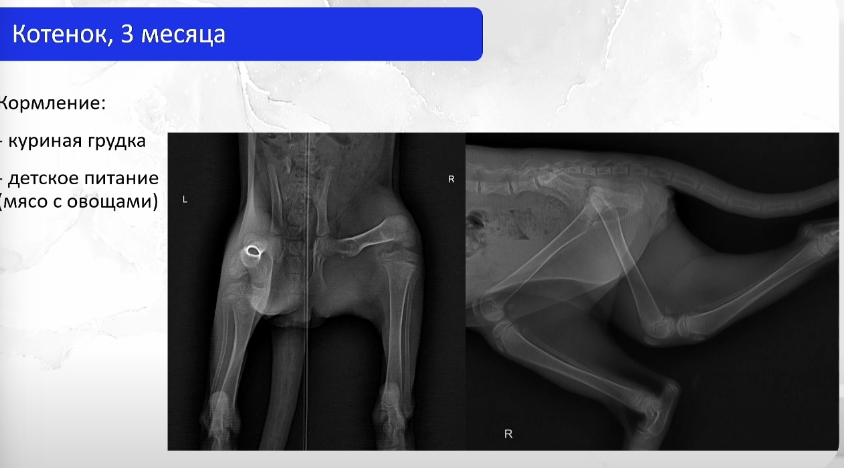

Трехмесячного котенка принесли в ветклинику на обследование, и уже первый рентгеновский снимок удивил ветврачей. Кости животного были почти прозрачные. Причина оказалась в рационе. Хозяева давали котенку куриную грудку и детское пюре.

Что показал снимок

На снимке специалист заметила системное снижение плотности костных структур. Скелет выглядел менее крепким, чем должен быть у животного такого возраста. Также возникло подозрение на сужение таза, рассказала ветеринарный врач-диетолог Дарья Маслакова из сети ветклиник «Белый клык».

Бедренные кости, коленные и скакательные суставы, а также кости плюсны не демонстрировали значимых патологий.

Такая картина характерна для вторичного алиментарного гиперпаратиреоза — заболевания, возникающего из-за длительного нарушения баланса питательных веществ.

Так организм пытается восполнить дефицит. Сердце и мозг для него важнее костей. Постепенно они теряют плотность, становятся хрупкими и деформируются. Поэтому на рентгене у котенка скелет выглядел почти прозрачным.

Особенно коварна эта ситуация потому, что уровень кальция в анализах крови может долгое время оставаться нормальным. Организм поддерживает его за счет разрушения костной ткани, и проблему можно увидеть только на рентгенологических снимках.